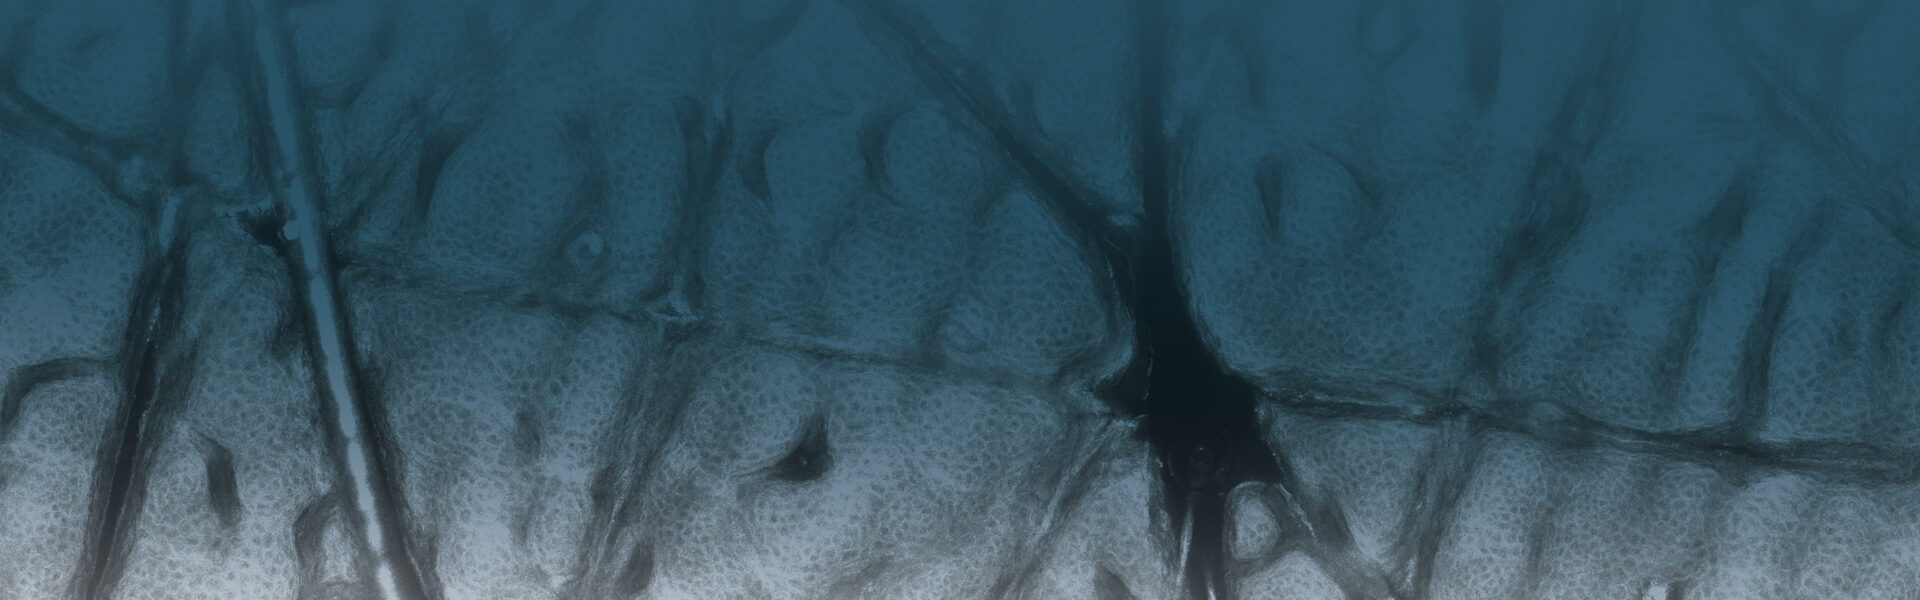

Our In Vivo product line allows for a real-time and non-invasive Instant Optical Biopsy from the epidermis to the upper dermis. With the VivaScope confocal laser scanning microscopy the cell morphology of the skin layers are displayed in high resolution.